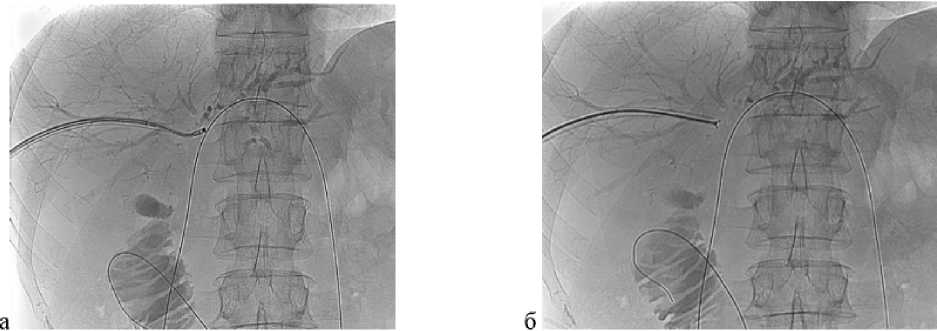

Всем пациентам выполнена верификация онкологического процесса с применением оригинальной запатентованной методики видеоассистированной внутрипротоковой щипковой биопсии под рентгеноскопическим контролем [23]. Сущность метода заключается в чрескожной антеградной холангиоскопии как метода определения истинного расположения опухоли. На проводнике производили удаление НВЧЧХД, далее по проводнику под рентгеноскопическим контролем за дефект контрастирования заводили интродьюсер 10 F, проводник удаляли. Через интродьюсер за зону опухолевой окклюзии вводили ультратонкий эндоскоп CMOS – серия 11102 СМ – Karl Storz (Германия; 2,9 мм = 8,7 F). После выявления истинного расположения опухоли интродьюсер подводили к концевой части эндоскопа. После чего эндоскоп удаляли, фиксируя положение интродьюсера. Далее через интродьюсер заводили эндоскопические щипцы для биопсии с шагом 1,5–2 мм и выполняли биопсию под рентгеноскопическим контролем (рис. 1). Во всех случаях объем полученного биоматериала был достаточным для гистологического и иммуногистохимического исследования.

Рис. 1. Видеоассистированная внутрипротоковая щипковая биопсия под рентгеноскопическим контролем. а — рентгенограмма: ультратонкий эндоскоп установлен в месте выявленной опухоли на уровне конфлюенса общего печеночного протока; б — рентгенограмма: прицельная щипковая внутрипротоковая биопсия опухоли общего печеночного протока с использованием биопсийных щипцов